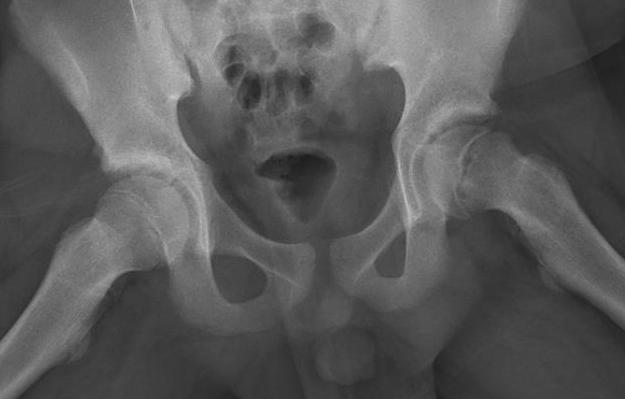

AP Xray

Widened eipiphysis

Klein's Line

- line along superior neck should transect part of epiphysis

Mild slip with failure of Klein's line to transect epiphysis